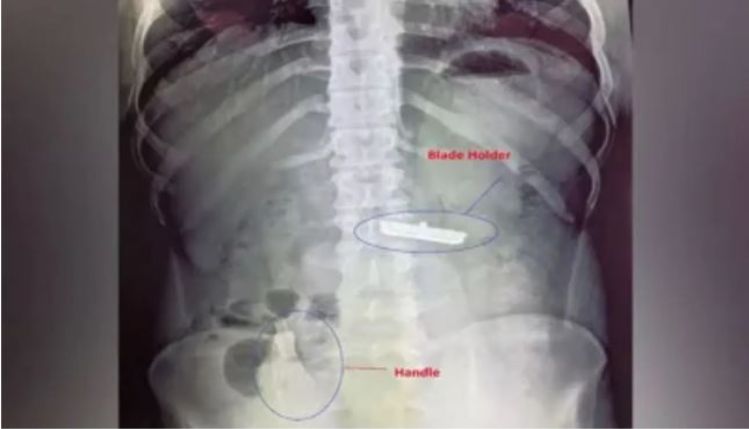

ନୂଆଦିଲ୍ଲୀ: ଦିଲ୍ଲୀରେ ଏକ ଆଶ୍ଚର୍ଯ୍ୟଜନକ ଘଟଣା ସାମ୍ନାକୁ ଆସିଛି । ଜଣେ ୨୦ ବର୍ଷ ବୟସ୍କ ଯୁବକ ଏଠାରେ ଥିବା ସାର୍ ଗଙ୍ଗା ରାମ ହସ୍ପିଟାଲରେ ପହଞ୍ଚିଥିଲେ । ଯୁବକ ଜଣକ ତାଙ୍କ ପେଟରେ ଏକ ରେଜର ଥିବା ବିଷୟରେ କହିଥିଲେ । ପ୍ରଥମେ ଡାକ୍ତରମାନେ ଏହାକୁ ବିଶ୍ୱାସ କରିନଥିଲେ । କିନ୍ତୁ ତାଙ୍କ ପେଟର ଏକ୍ସ-ରେ କରିବା ପରେ ସମସ୍ତେ ଆଶ୍ଚର୍ଯ୍ୟ ହୋଇଯାଇଥିଲେ ।

ବ୍ଲେଡ୍ ଏବଂ ରେଜର୍ ହ୍ୟାଣ୍ଡଲ୍ ଯୁବକଙ୍କର ପେଟରେ ଦୁଇଟି ଅଂଶରେ ସ୍ପଷ୍ଟ ଦେଖାଯାଉଥିଲା । ହ୍ୟାଣ୍ଡେଲଟି ତାଙ୍କ ଅନ୍ତନଳୀରେ ଅଟକି ଯାଇଥିବାବେଳେ ବ୍ଲେଡ ତାଙ୍କ ପେଟରେ ଲାଗିଥିଲା । ତୁରନ୍ତ ଏହି ବିଷୟରେ ବରିଷ୍ଠ ଡାକ୍ତରମାନଙ୍କୁ ଅବଗତ କରାଯାଇଥିଲା ଏବଂ ଯୁବକଙ୍କ ପେଟରୁ ରେଜରକୁ ବାହାର କରିବାପାଇଁ ଡାକ୍ତରଙ୍କ ଏକ ଟିମ୍ ଗଠନ କରାଯାଇଥିଲା । ବହୁ ପରିଶ୍ରମ ପରେ ଡାକ୍ତରମାନେ ଯୁବକଙ୍କ ପେଟରୁ ବ୍ଲେଡ ଏବଂ ଏହାର ହ୍ୟାଣ୍ଡେଲ ବାହାର କରିଥିଲେ । ବର୍ତ୍ତମାନ ଅସ୍ତ୍ରୋପଚାର ପରେ ଯୁବକ ସମ୍ପୂର୍ଣ୍ଣ ସୁସ୍ଥ ଥିବା ସୂଚନା ରହିଛି ।